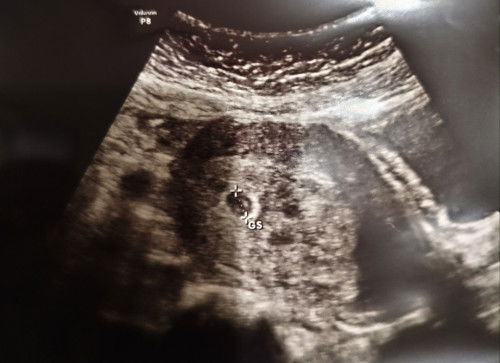

Kena ada 3 lingkaran di hasil USG

Bun, aku kemarin USG. karena saking kagetnya kalau ternyata aku benar2 hamil (soalnya jaraknya dekat dgn anak kedua ku), jd aku ga fokus. sampai rumah , aku baru sadar kok hasil usg nya ada buletan 3 gitu ya bun. ada yg tau ga ya bun? soalnya kmrn dokternya ga bilang apa2, cm blg letaknya bagus. sesuai dengan hpht. tp blm ada janinnya karena msh 5w🙏